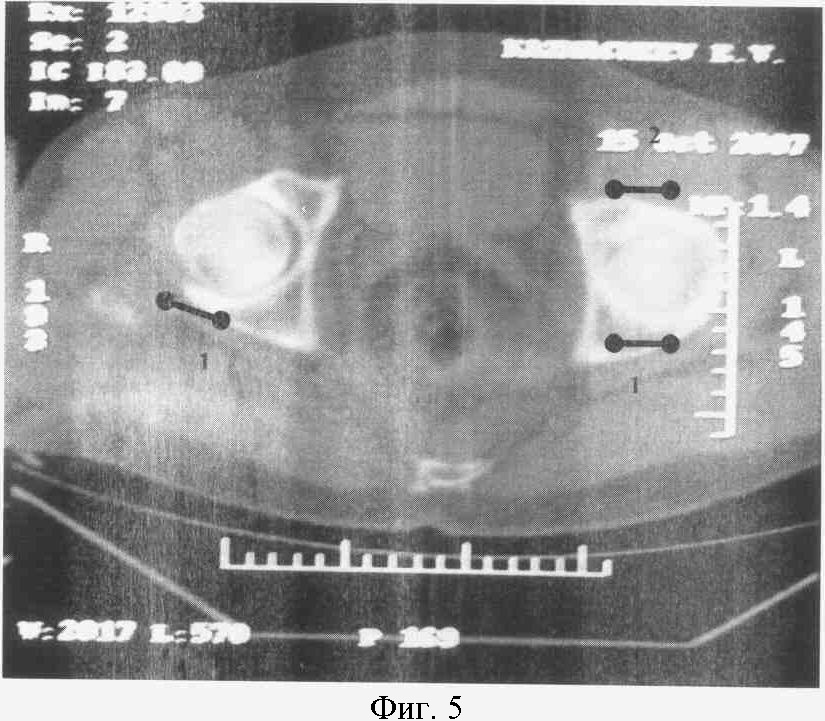

На фиг.5. представлен КТ срез на уровне верхней трети головки бедра больного К.

Справа: 1-я стадия коксартроза с локализацией участков компрессии в заднем отделе сустава (1).

Слева: 2-я стадия коксартроза с кистевидной перестройкой с локализацией участков компрессии в заднем (1) и переднем отделах сустава (2).